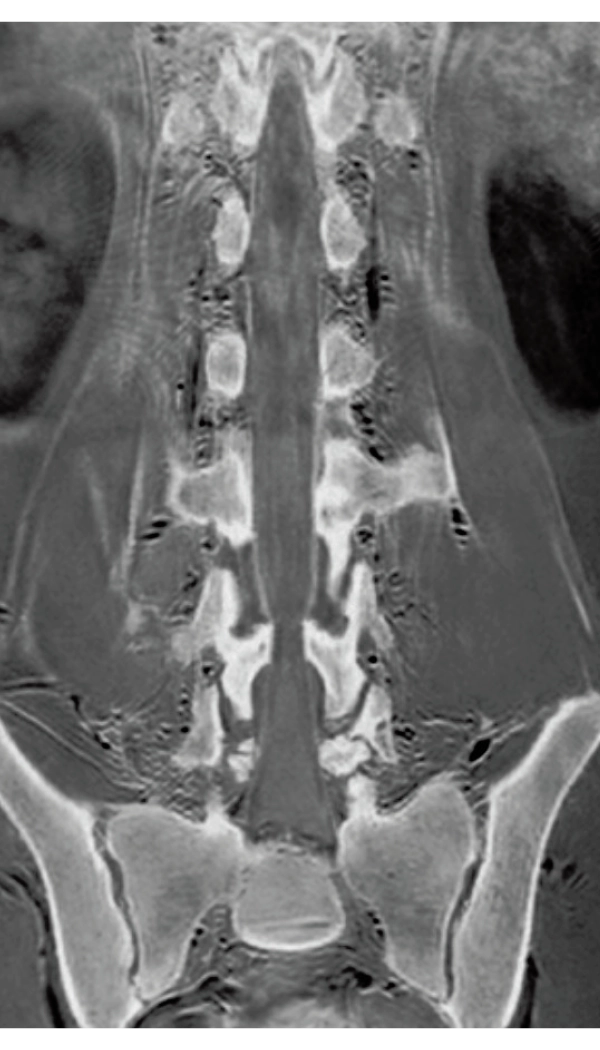

3D T1WI COR

2.2×1.5×1.5 mm

3st total scan time 0:54